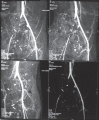

CT angiography showing thrombosis of right common iliac artery and proximal femoral artery